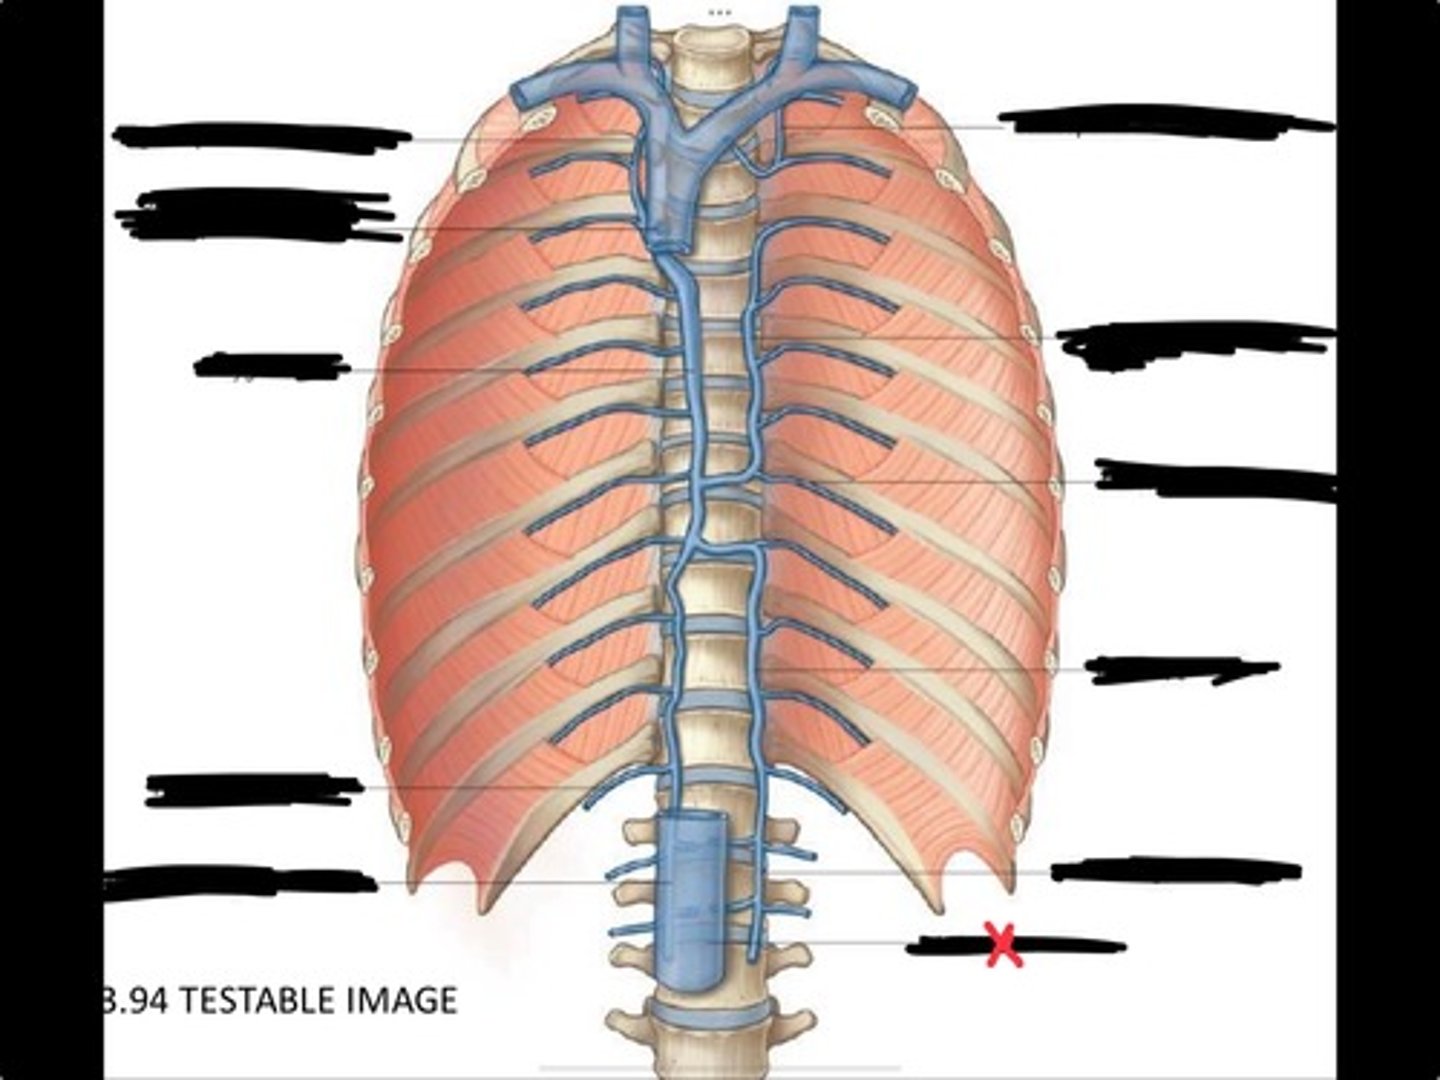

Right ascending lumbar vein

Right subcostal vein

Azygos vein

Opening of the azygos vein into superior vena cava

Right superior intercostal vein

Left superior intercostal vein

Accessory hemiazygos vein

Posterior intercostal vein

Hemiazygous vein

Ascending lumbar vein

Inferior vena cava

Diaphragm

Inferior vena cava